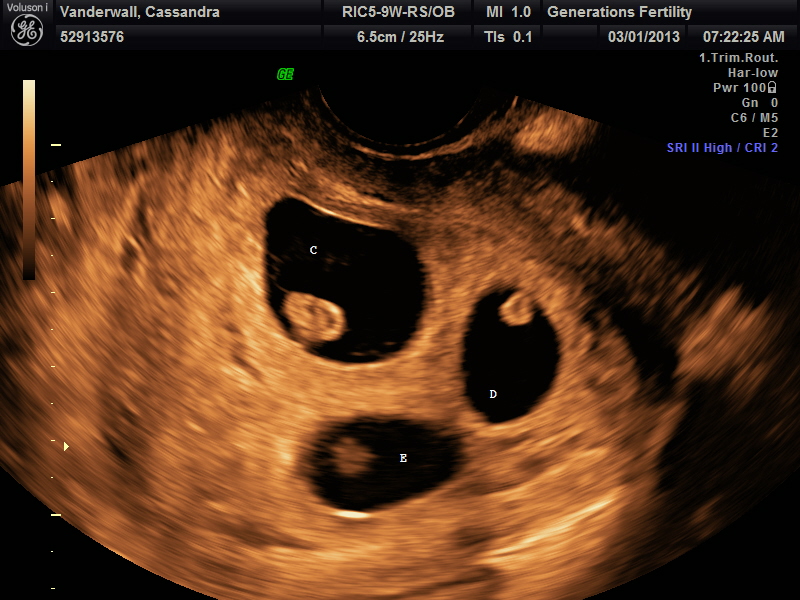

The next check-point was at our first ultrasound to see what was causing all of this raucous. We were greeted by not one, not two, not even three, but five beating hearts at our 7-week check-up. It looks like my body donated a few more follies than suspected. Those that have been in this position know the next words out of your doctor’s mouth are not, “Congratulations!” But, instead, “we need to have a conversation about selective reduction.” I, honestly, in my wildest dreams never thought that following the moment that I witnessed the gift of life, someone would be asking to take it away. The doc then began handing over research article after article on the dangers of not reducing and my husband and I were quickly referred to the high risk clinic.